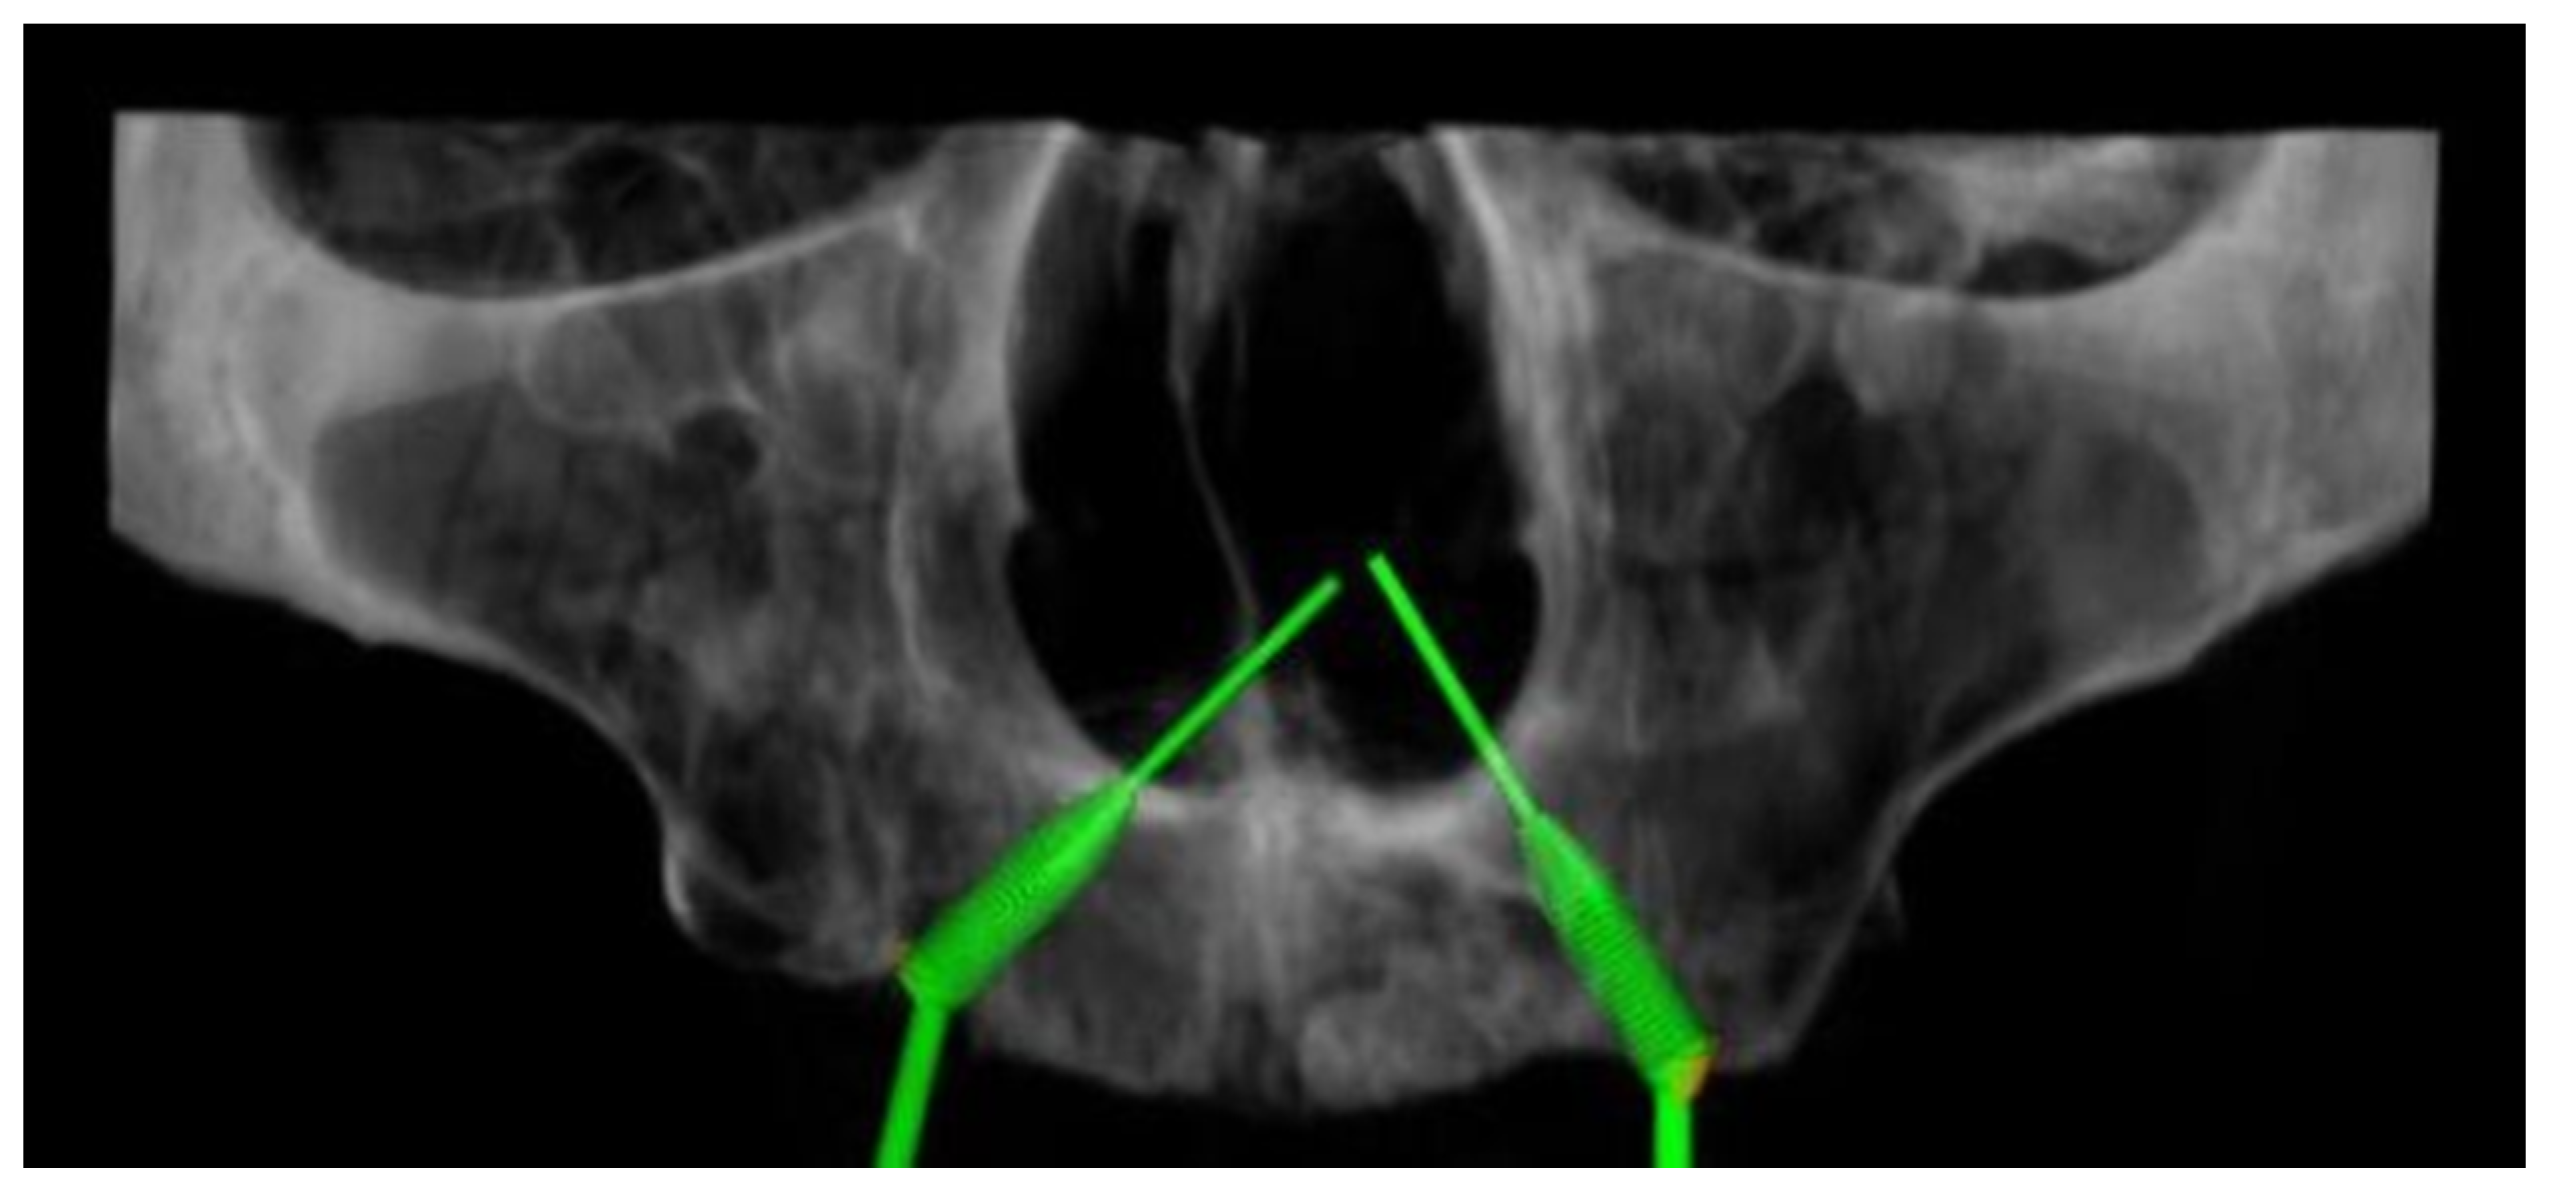

2.2. Virtual Iuxtameatal Implant Positioning